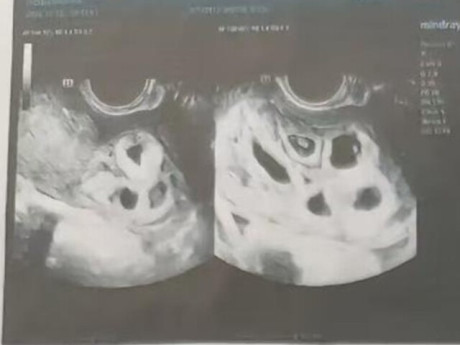

Mới đây, các y bác sĩ tại Bệnh viện Phụ sản Hà Nội đã mổ đẻ thành công cho 1 ca sinh 3 IVF đặc biệt. Cả 3 bé chào đời khỏe mạnh với cân nặng đều trên 2,3kg.

Mang tam thai là một hành trình đầy thử thách, đòi hỏi sự theo dõi sát sao và chăm sóc đặc biệt. Sau hành trình IVF đầy gian nan, mẹ Đ.H.L (31 tuổi , Hải Phòng) đã vỡ òa hạnh phúc khi chào đón ba thiên thần nhỏ đáng yêu, 1 bé trai và 2 bé gái. Đặc biệt, hai bé gái là cặp song sinh cùng trứng vô cùng hiếm gặp.

Đến tuần thứ 36, ba bé đã chào đời khỏe mạnh, với cân nặng lần lượt là 2350 gram, 2450 gram và 2500 gram. Ca phẫu thuật được thực hiện bởi Ths.BSCKII Trần Ngọc Đính - Trưởng khoa Tự nguyện D5 - và ekip đã diễn ra thuận lợi, mẹ tròn con vuông.